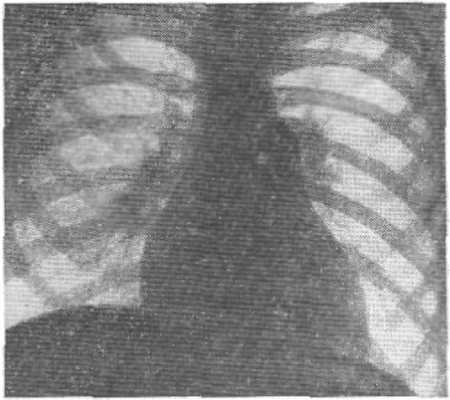

Рентгенодиагностика

Рентгенологические признаки зависят от характера бронхо-легочного заболевания, а при его отсутствии соответствуют картине первичной легочной гипертензии. При рентгеноскопии видна усиленная пульсация легочного ствола и крупных ветвей легочной артерии и, как и на рентгенограммах (рис.), определяются выбухание дуги легочного ствола, увеличение калибра артерий в корнях и прикорневых зонах легких, «ампутация» теней сегментарных сосудов и отсутствие легочного рисунка в периферических отделах легочных полей. В правом переднем косом положении отмечаются выбухание легочного конуса и увеличение диаметра круглой тени левой легочной артерии в ортогональной ее проекции. В левом переднем косом положении «аортальное окно» закрыто тенью расширенного легочного ствола; обычно, как и в боковом положении, имеются признаки увеличения правого желудочка.

Углубленное рентгенологическое исследование (томография, электрокимография, ангиокардиография) выявляет при Айерсы синдроме расширение только артериальных сосудов, в то время как легочные вены не расширены.